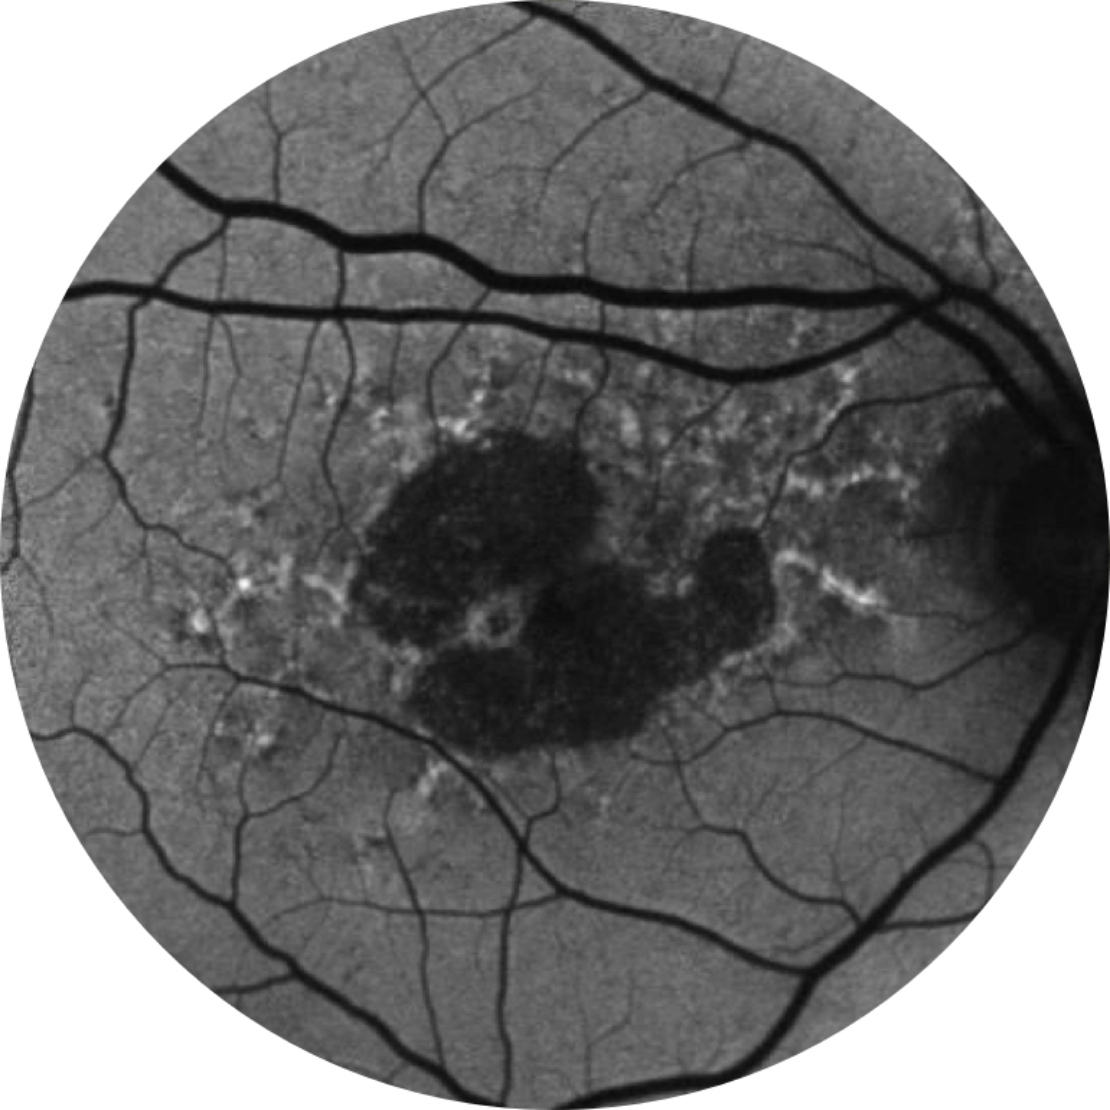

Autofluorescenza normale del fondo oculare di una retina

L’angiografia con autofluorescenza del fondo oculare è attualmente una tecnologia di imaging standard per visualizzare l’epitelio pigmentato retinico (EPR) nell’atrofia geografica.20